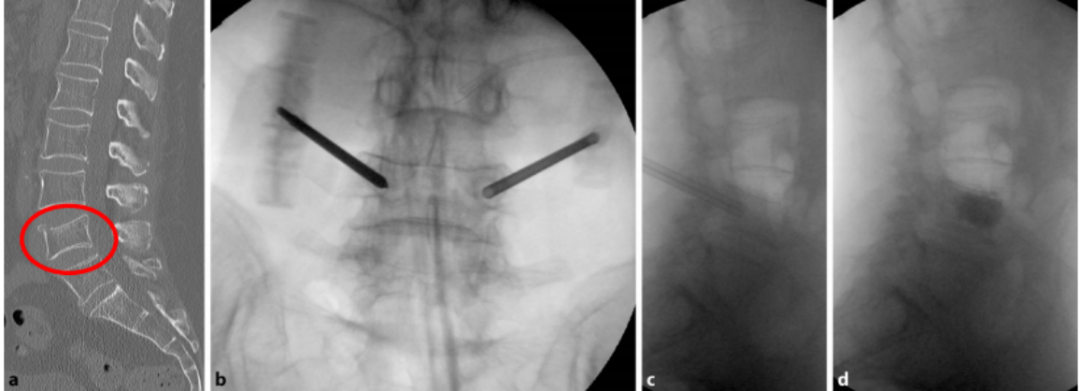

椎体强化手术,包括椎体成形术(PVP)和经皮球囊扩张椎体后凸成形术(PKP),是目前最常用的微创手术治疗方法。通过经皮向骨折椎体注射骨水泥,能够迅速缓解疼痛,增强病椎的强度和刚度,防止椎体进一步塌陷和畸形,而且没有传统开放手术内固定带来的手术创伤以及远期可能出现的内固定失败。PKP还可通过球囊扩张使压缩骨折得到一定程度的复位,球囊取出后在椎体内形成的空腔有利于骨水泥低压力注入,有效降低骨水泥渗漏率。

PVP

椎体成形术(PVP):

经皮椎体成形术(percutaneous vertebroplasty,PVP)是经皮由椎弓根置入,骨水泥注入椎体,从力学上增强其结构强度。

椎体成形术(PVP)病例